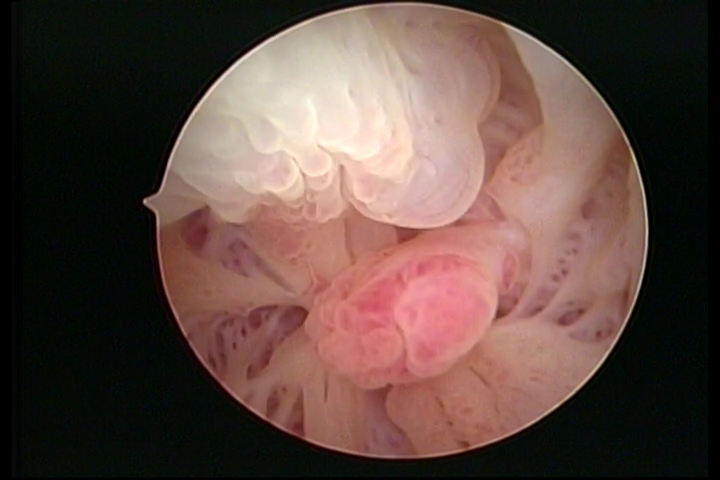

First part or proximal section or lower section:

During the proliferative phase, a light, crystalline mucus with a low adherence to the scope is found. The crypts and buds are a little swelled and vascularized, microvesicular, resembling grape clusters.